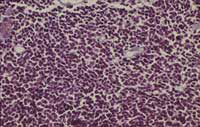

髓母细胞瘤是常见的原始神经外胚层肿瘤(PNET),占儿童期全部脑肿瘤的25%以上。髓母细胞瘤常见于小脑,位于大脑的下背部,并引起包括头痛,恶心,呕吐和肌肉协调问题(共济失调)的症状。与其他原发性脑肿瘤不同,如果不进行治疗,髓母细胞瘤倾向于扩散到整个神经系统。

在不常见的情况下,髓母细胞瘤可能扩散到神经系统之外,扩散到淋巴结,骨髓,肺或身体的其他部位。在许多情况下,仅通过手术和放射疗法即可对其进行治疗。它们是生长迅速的肿瘤,但是由于它们对放射疗法和化学疗法敏感,因此通常可以合适地治疗。